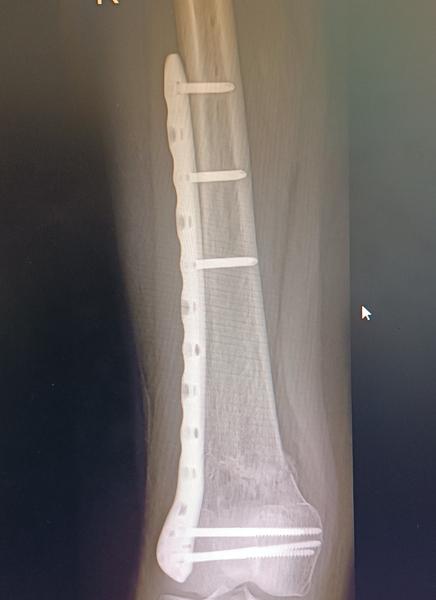

Dobrý deň prosím ak tu taky su napíšte mi ako ste to zvladali cele ...ja mam v nohe stehenna kosť platničku plus skrutky o mesiac mam planovanu operáciu na vybratie materiálu mam 35 rokov môžem si to ešte premyslieť a zrušiť mne platnička nerobi nejake výrazne problemy ,nohu mam akurat taku oťaženu krivam stale ale ja som vďačná že vôbec chodím..v zime ma bolievalo koleno pri dlhej chodzi neviem či z platničky alebo tym že noha bola zlomena ..nepovedia mi to ani lekari ani ty sa nezhodnu v tom či platničku nechať alebo vybrať a ja som s toho na prašky čo je lepšia možnosť 🥺😢 bojim sa operacie hrozne moc mam doma dve male deti desim sa toho zas prechádzať tým čím pred vyše rokom pre mňa to celé bola trauma , ale zas sa bojim aj toho aby mi to neskôr nerobilo problémy momentálne som ešte na rodičovskom a keď nastupim do práce by som možno mohla byť už fit keby mi to teraz vyberu neviem čo robiť som zufala😔